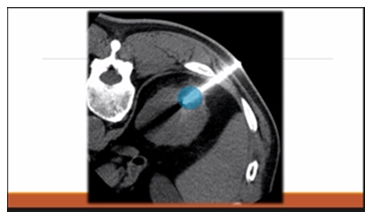

來自日本國立癌癥研究中心中央病院放射科診斷和IVR中心主任-菅原俊佑介紹了“罕見癌癥的消融治療”。消融治療屬于介入治療IVR ,是在觀看超聲或 CT 等圖像的同時將針從體表插入病灶,通過改變溫度殺死癌細胞的一種方式,可以在局部麻醉下進行。具體有兩個類別:使用無線電波或微波等高頻電磁波將病灶溫度提高到 80 ~90°C 來燒灼病變的方法,以及使用氬氣將病灶冷凍到約 -160°C以殺死癌細胞的冷凍療法。醫保范疇內的癌癥消融治療中,微波消融治療僅適用于肝癌,射頻消融治療適用于肝癌、腎癌、乳腺癌、肺癌、骨癌、軟組織癌和盆腔內癌癥,而冷凍治療僅適用于腎癌。

微波消融治療中使用的針比其他消融治療中的針稍粗。針插入后,消融區域通過電流的功率和時間進行調節。而射頻消融治療時,消融范圍根據針的類型進行調整,目前在日本可以消融1~3厘米的范圍。

冷凍治療的針和微波消融的針差不多。在影像設備的引導下,將針插入患者體表,高壓氬氣在針內循環,針尖的溫度迅速下降破壞腫瘤。這種方式與射頻消融不同,主要優勢在于在治療實施的過程中可以實時檢測冷凍區域。